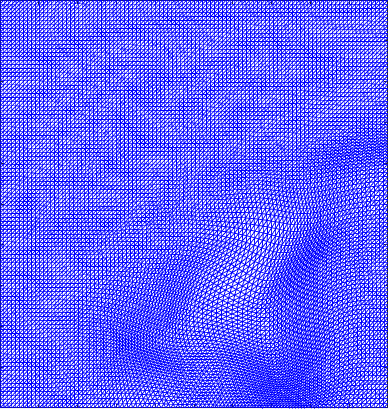

Figure 5 shows the ground truth and recovered maps of the registration maps in the last row of Table 4. It can be seen that ground truth low-rank mapping shown in Figure 5(a) resembles the recovered low-rank mapping shown in Figure 5(c). This again shows that we could obtain a meaningful mapping from the decomposition.

Figure 6 displays the 4 mappings as in Example 3 and 4. Again, we can see that after the decomposition of the Beltrami descriptor, the decpmposed mappings to large extent resemble the corresponding ones.